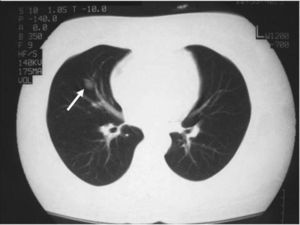

La paciente fue intervenida quirúrgicamente mediante cirugía transesfenoidal. El informe de anatomía patológica de la pieza fue de hipófisis normal. En la primera revisión tras la cirugía persistía la clínica y la bioquímica de hipercortisolismo. El informe de la radiografía de tórax de la consulta preanestésica describía una imagen de aspecto seudonodular en probable relación con falsa imagen secundaria a superposición de estructuras óseas y vasculares. En la radiografía de control persistía la imagen nodular de menos de 1 cm (fig. 1), que se confirma en la tomografía computarizada (TC) torácica, y se describía como un nódulo sólido de 11,6 × 16 mm en el lóbulo medio (fig. 2).